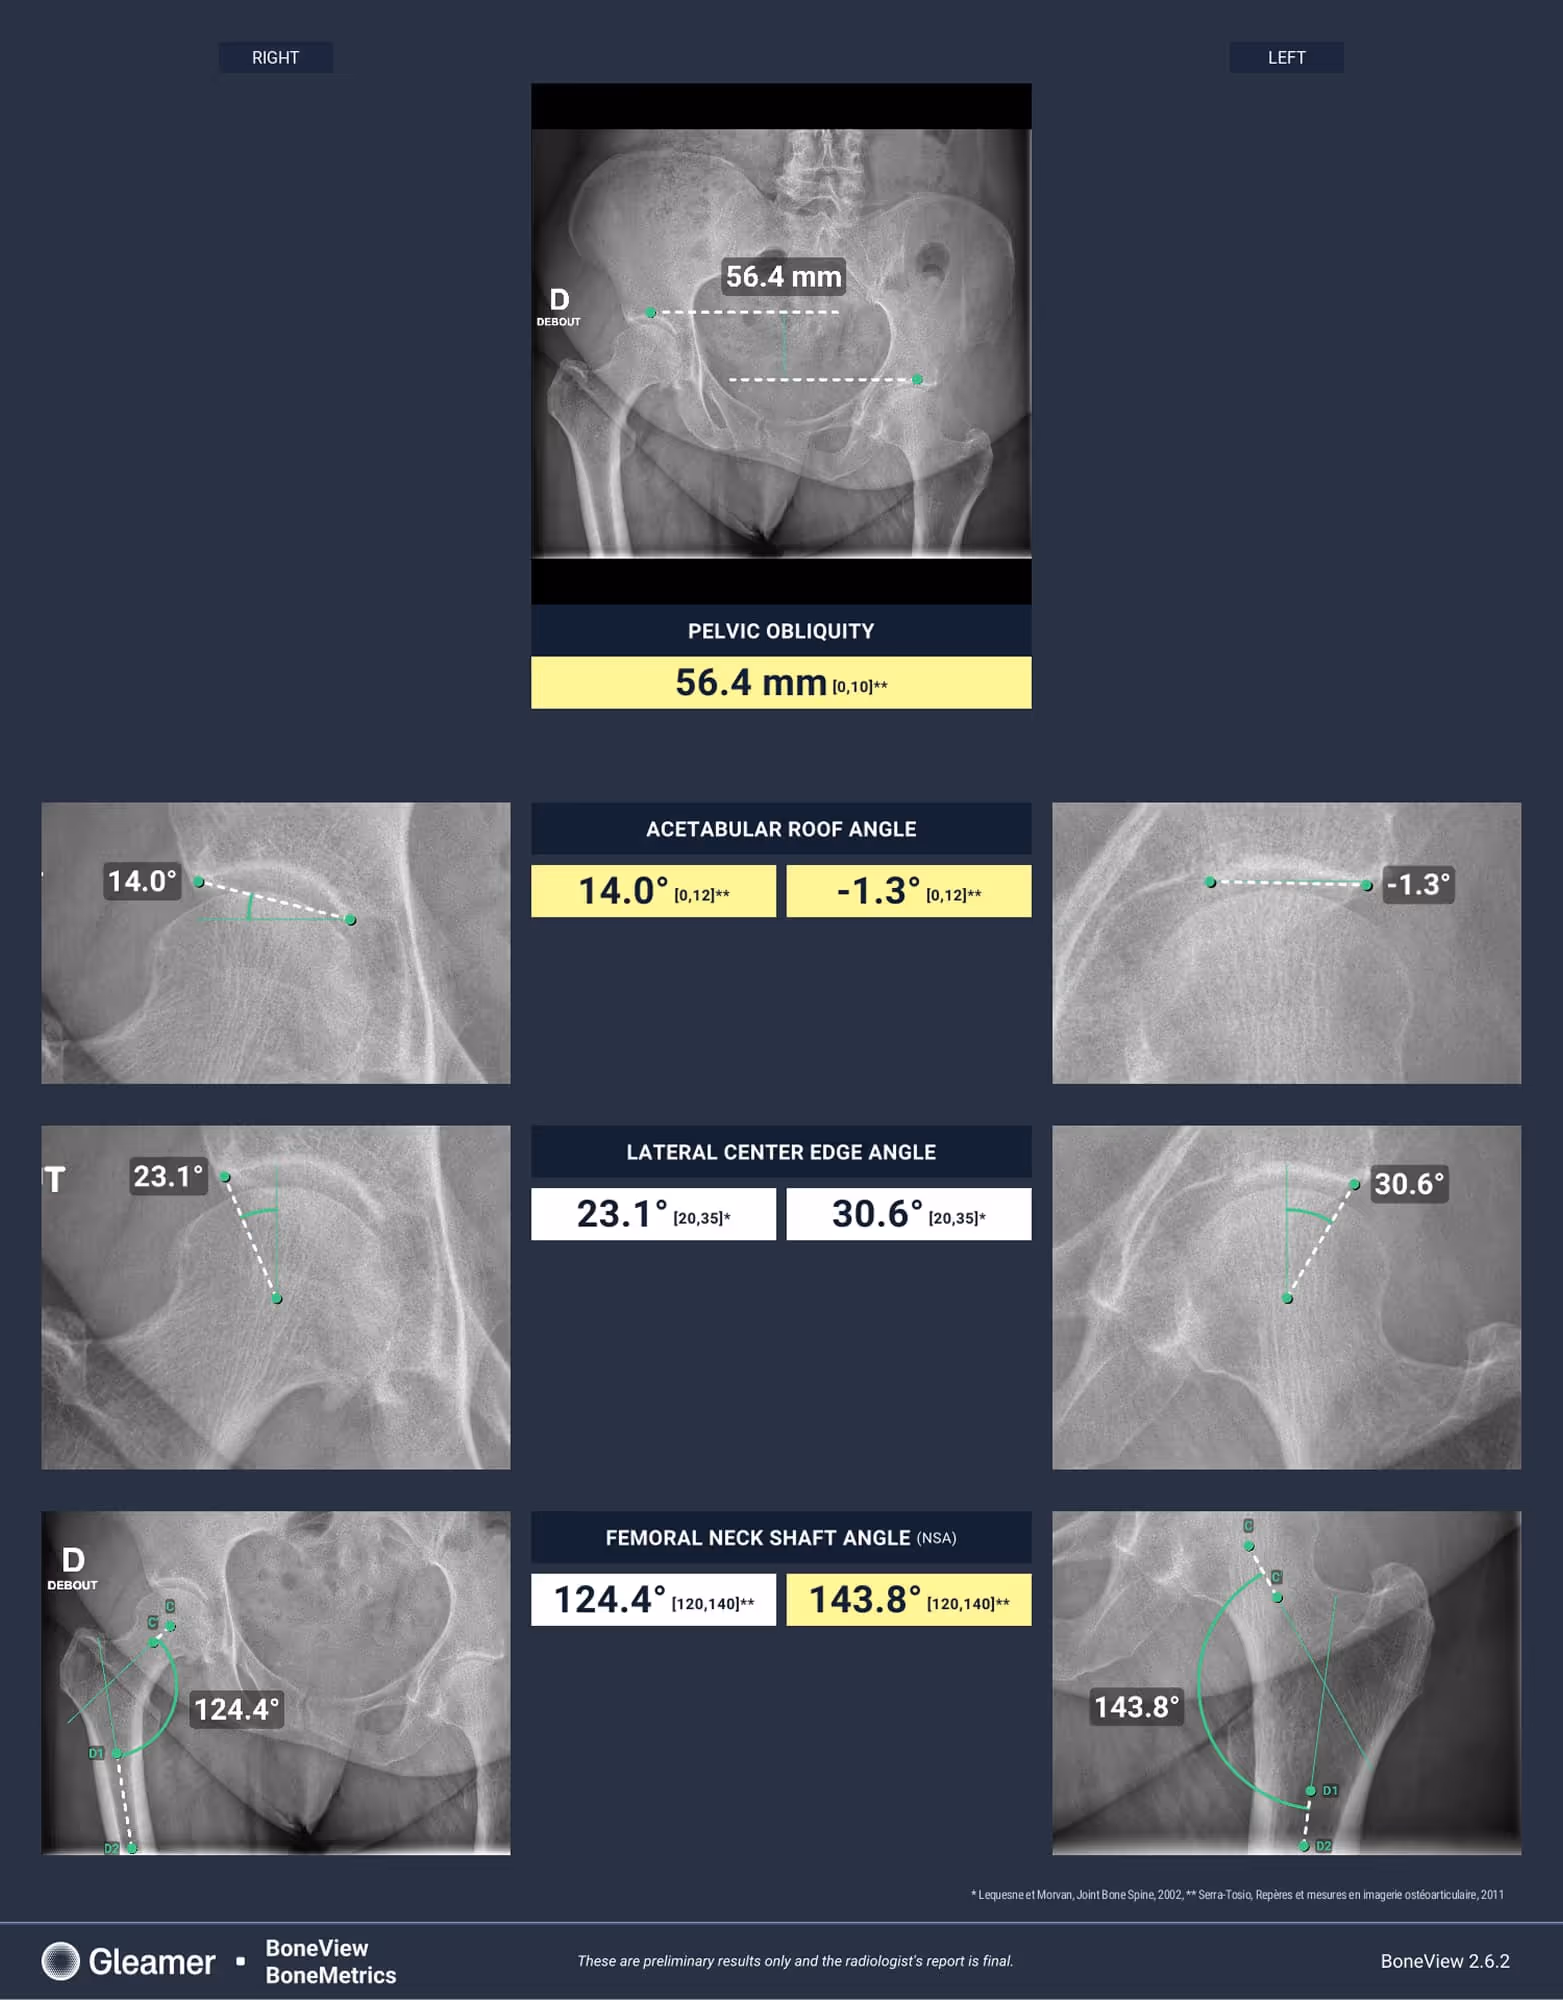

Indication

A 60-year-old female with a history of right hip coxoarthritis presents with left hip pain.

Results

BoneMetrics confirmed the presence of hip dysplasia and inequality of pelvic obliquity.